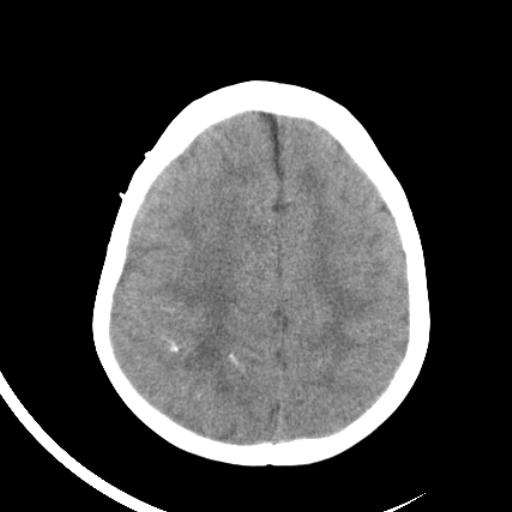

双侧脑室前后角周围白质片状低密度影,双侧侧脑室旁、双顶叶皮层及皮层下多个小原点状钙化灶,不除外torch感染。右顶叶脑回似乎较对侧大,建议mri检查以除外脑发育异常。

考虑:1、巨脑回畸形(皮质明显增厚+脑回明显增宽+白质减少)。

2、torch综合征(室管膜下钙化+白质内及皮髓质交界处多发钙化)。